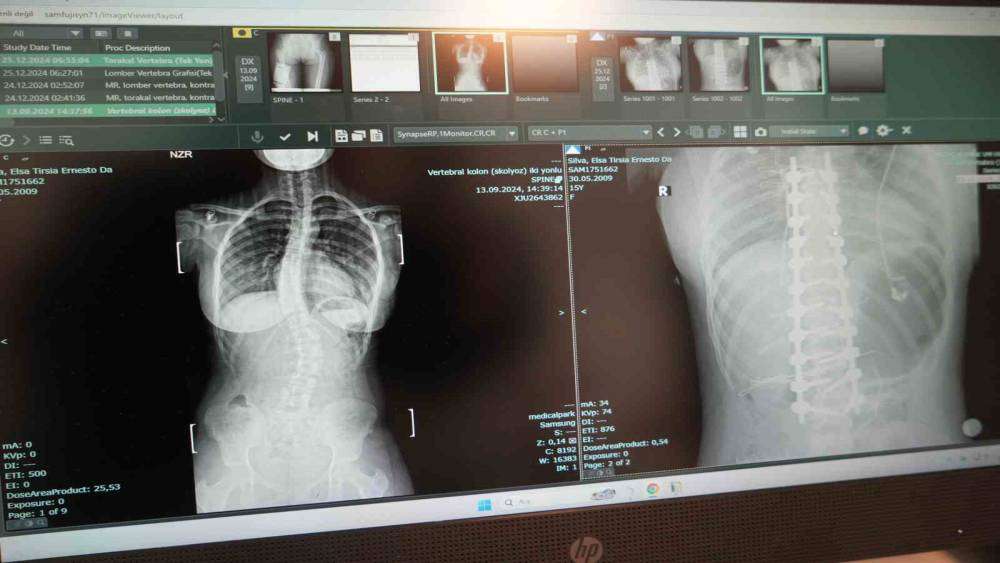

Omurgasında 45 derece eğrilik bulunan skolyoz hastası 15 yaşındaki Elsa Silva, Angola’dan Samsun’a gelerek burada yapılan ameliyatla şifa buldu.Angola’dan Samsun’a şifa bulmak için gelen skolyoz hastası 15 yaşındaki Elsa Silva’ya VM Medical Park Samsun Hastanesi’nde skolyoz ameliyatı yapıldı. Yapılan ameliyat ile şiddetli ağrılarından ve bel eğriliğinde kurtulan Elsa Silva, çok mutlu olduğunu söyledi.Hastanın ameliyatını gerçekleştiren Ortopedi ve Travmatoloji Uzm. Prof. Dr. Turgut Nedim Karaismailoğlu, "Hastamızda skolyoz mevcuttu. 2 ay önce bize geldi. Angola’da yaşıyorlar. Geldiğinde 45 derece bel eğriliği mevcuttu. Yaşı 15’ti ve bu yaşta ameliyat olması gerekiyordu. Hasta, ameliyattan sonra ikinci gün ayağa kaldırıldı. Üçüncü günde taburcu edildi. 15. günde dikişleri alındı. Bu ameliyatlar ağır ve dikkat isteyen ameliyatlardır. Bu konuda Türkiye’de son dönemde çalışan uzman sayısı arttı. Samsun’da bu imkan olduğu için çevre ülkelerden gelen hasta sayısında artış mevcut. Biz de onlara elimizden geldiğince cevap vermeye çalışıyoruz" dedi.Elsa Silva ise ameliyat olduktan sonra kendisini daha rahat ve iyi hissettiğini söyledi.

Omurgasında 45 derece eğrilik bulunan skolyoz hastası 15 yaşındaki Elsa Silva, Angola’dan Samsun’a gelerek burada yapılan ameliyatla şifa buldu.

Angola’dan Samsun’a şifa bulmak için gelen skolyoz hastası 15 yaşındaki Elsa Silva’ya VM Medical Park Samsun Hastanesi’nde skolyoz ameliyatı yapıldı. Yapılan ameliyat ile şiddetli ağrılarından ve bel eğriliğinde kurtulan Elsa Silva, çok mutlu olduğunu söyledi.

Hastanın ameliyatını gerçekleştiren Ortopedi ve Travmatoloji Uzm. Prof. Dr. Turgut Nedim Karaismailoğlu, "Hastamızda skolyoz mevcuttu. 2 ay önce bize geldi. Angola’da yaşıyorlar. Geldiğinde 45 derece bel eğriliği mevcuttu. Yaşı 15’ti ve bu yaşta ameliyat olması gerekiyordu. Hasta, ameliyattan sonra ikinci gün ayağa kaldırıldı. Üçüncü günde taburcu edildi. 15. günde dikişleri alındı. Bu ameliyatlar ağır ve dikkat isteyen ameliyatlardır. Bu konuda Türkiye’de son dönemde çalışan uzman sayısı arttı. Samsun’da bu imkan olduğu için çevre ülkelerden gelen hasta sayısında artış mevcut. Biz de onlara elimizden geldiğince cevap vermeye çalışıyoruz" dedi.